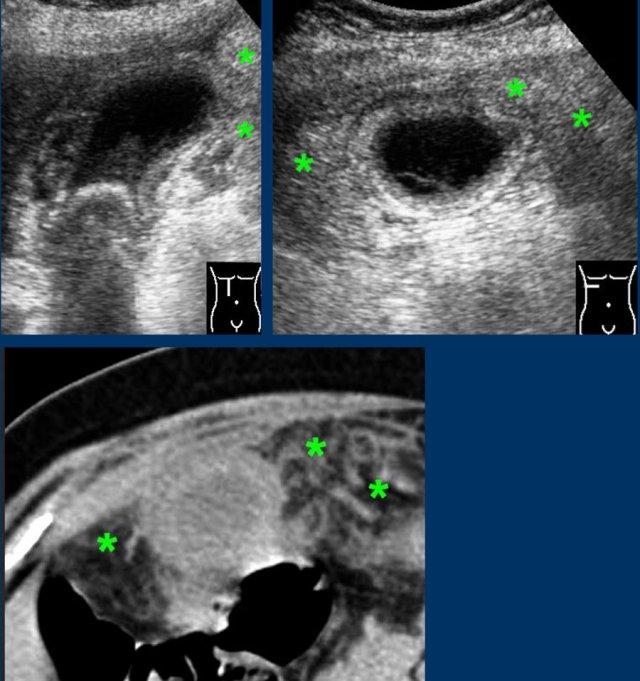

Dấu hiệu chứng nhân thầm lặng của cơn đau quặn mật ở sáu bệnh nhân khác nhau.

Siêu âm được thực hiện 6-12 giờ sau cơn đau.

Tất cả bệnh nhân đều không có triệu chứng tại thời điểm siêu âm.